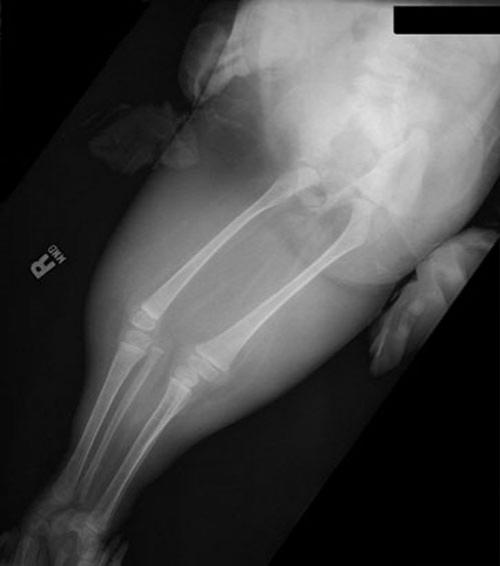

Большинство детей с «сиреномелией» - редким врожденным пороком развития – так называемым «синдромом русалки» погибают в первые часы после появления на свет из-за многочисленных сопутствующих дефектов развития…В настоящее время в мире известны три случая спасения детей с подобным синдромом – это американка Тифани Йоркс, успешно перенесшая операцию по разделению ног 19 лет назад,трехлетняя перуанская девочка Милагрос Серрон, последняя операция по разделению ног которой была проведена летом этого года, и Шилох Пепин, единственная, кого так и не прооперировали…

Кроме сросшихся ног у девочки при рождении не досчитались мочевого пузыря, матки, толстого кишечника, влагалища…У неё была лишь одна недоразвитая почка и один яичник…